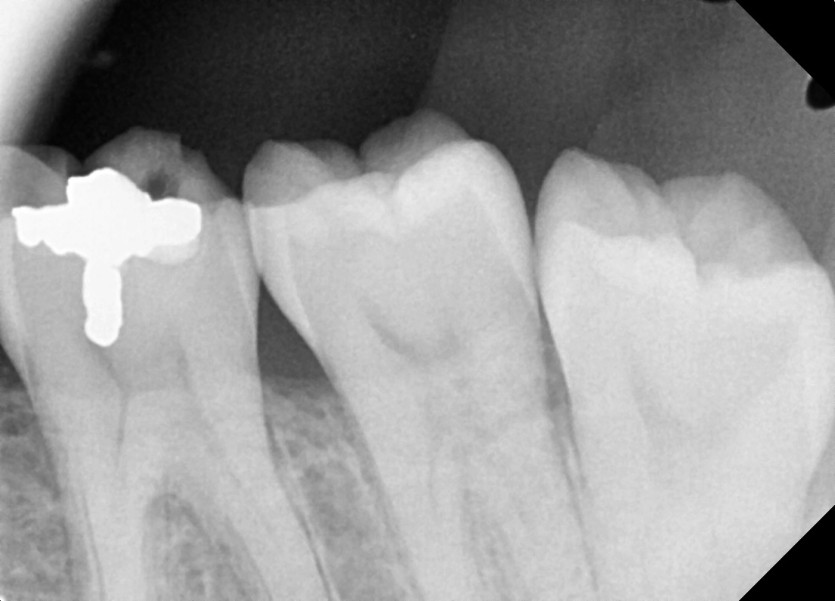

#38 사랑니 발치

구강 외과 전문의가 당일 발치했습니다.